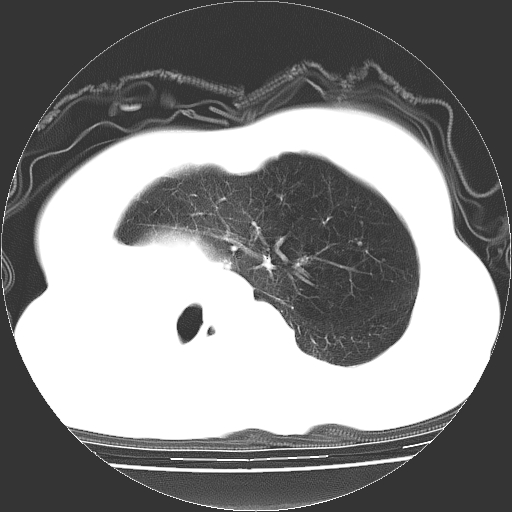

标题: CT23991:女,72岁,咳嗽、憋气一周。 [打印本页]

女,72岁,咳嗽、憋气一周,十年前曾患肺结核及胸膜结核。

右侧毁损肺,右侧纵隔疝,左肺代偿!

右侧肺硬变,左肺代偿气肿。

右侧肺毁损,左肺代偿性肺气肿,纵隔疝。